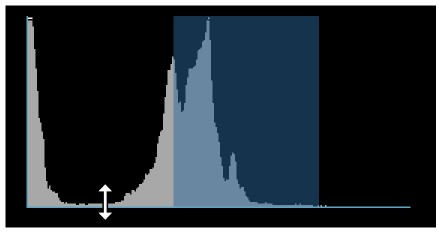

A windowing histogram is a graphical representation of the distribution of intensity values in an image. It displays the number of pixels at each intensity level, allowing users to adjust the brightness and contrast by setting a window around a range of intensity levels. By adjusting the position and width of the window, the user can optimize the image for their specific needs and better visualize the image features.

To change the window width, press and drag the left or right edge of the rectangular area representing the window.

To change the position or the window center, press and hold on the rectangular area and drag in the desired direction.